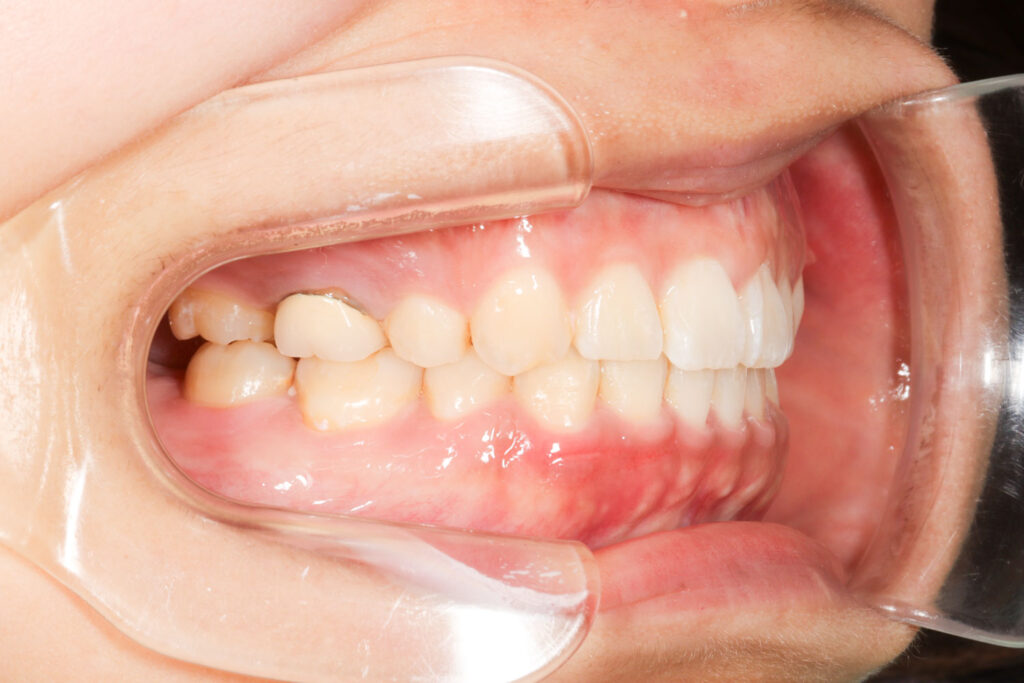

Before

After

年齢 10代

治療装置 上は裏側の矯正装置(ハーフリンガル)

治療内容 上下左右4本抜歯

治療期間 2年8か月

リスク 歯の移動に伴う痛み、歯肉退縮、歯根吸収、歯肉炎、虫歯

主訴 八重歯が気になる

症状 叢生(ガタガタ)

治療回数 33回程度

総額費用 125万円程度